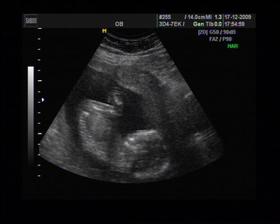

8/10 jsme se byli podívat u paní doktorky, zda testy nelhaly - a ono n e. Puclík měřil 0,37cm a co je důležité - srdíčko už funguje. Táta s Pepínem byli v ordinaci s námi, a když se na monitoru objevilo mimi, tak ho Pepíno pozdravil - udělal mu "ahoj" 🙂 oba nás to s Honzou dojalo. Další kontrola 22/10.